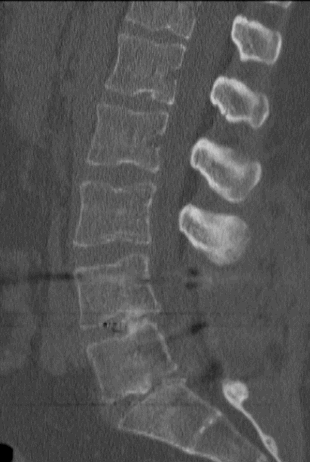

A csigolyaszámoló kurzorral címkézheti a csigolyákat és a csigolyaközöket. Ezek az előre meghatározott címkék saját megfelelő helyükön jelennek meg a képeken minden ortogonális síkban.

Csigolyaszámolás beillesztéséhez:

A jobb egérgombbal a képernyőre kattintva megjelenik a csigolyaszámolás vezérlőpanelje. Ez a mező lehetővé teszi a felhasználó számára a csigolyák és csigolyaközök címkézésének visszaállítását, és új szintek kiválasztását.

A beállítások fül a következő opciókat tartalmazza, amelyek a kezelőpanel újraindításakor visszaállnak:

| A csigolyaszámolás beállításai | Leírás |

L6-tal együtt |

L6-tal együtt L5 után |

Ellenkező irány |

Ha engedélyezve van, a címkék ellenkező irányba haladnak |

Vonalak mutatása |

Megjeleníti a tartóvonalakat a címkétől a fókuszpontig |

Panel automatikus elrejtése |

Az első csigolyaszámolás megrajzolása után automatikusan elrejti a csigolyaszámolás vezérlőpaneljét. |

Axiális, coronális, szagittális |

A csigolyaszámolások minden képen megjelennek a relatív síkban. A kép annotálásának időpontjában érvényes. |

Alkalmazott sík |

A címkéket ugyanabban a síkban jeleníti meg a képeken, mint a gerinc annotálásához használt sík. |

A megadott címkék ortogonális képeken való elhelyezéséhez az ábrának a fókuszponttól meghatározott távolságban kell metszenie a képet, amely ezután megjelenik a metszési síkban. A csigolyaszámolások automatikusan megjelennek az összes ortogonális képen. Ha a referenciakocka nincs előre meghatározva, a képeket egyenként kell címkézni. Ha a fókuszpont a megadott távolságon kívül esik, nem jelenik meg címke.